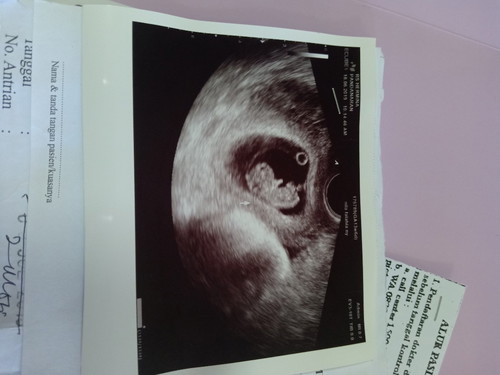

Bunda... Mau tanya.. Itu di hasil usg ku kok ada lingkaran kecil dekat janin.. Itu apa ya?? Ada yg tau??